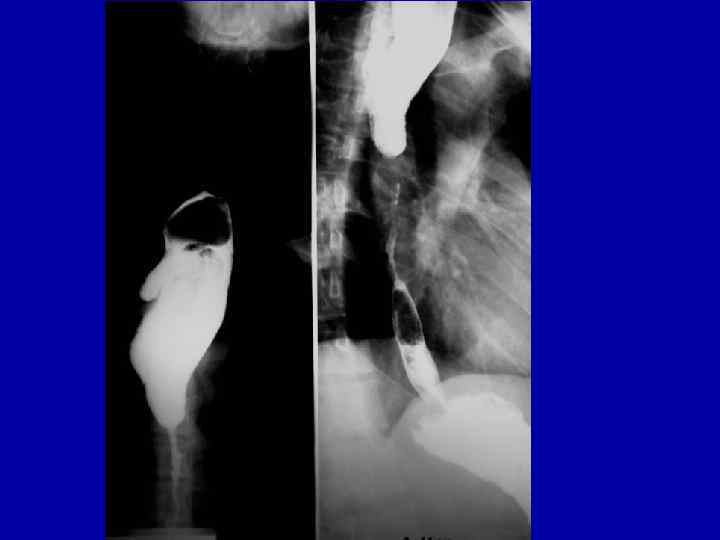

Больная К. 42 л. Диагноз: протяжённая ожоговая стриктура пищевода. Гастростома.

Протяженная ожоговая стриктура пищевода

Короткая ожоговая стриктура пищевода

Сочетанная рубцовая стриктура пищевода и глотки